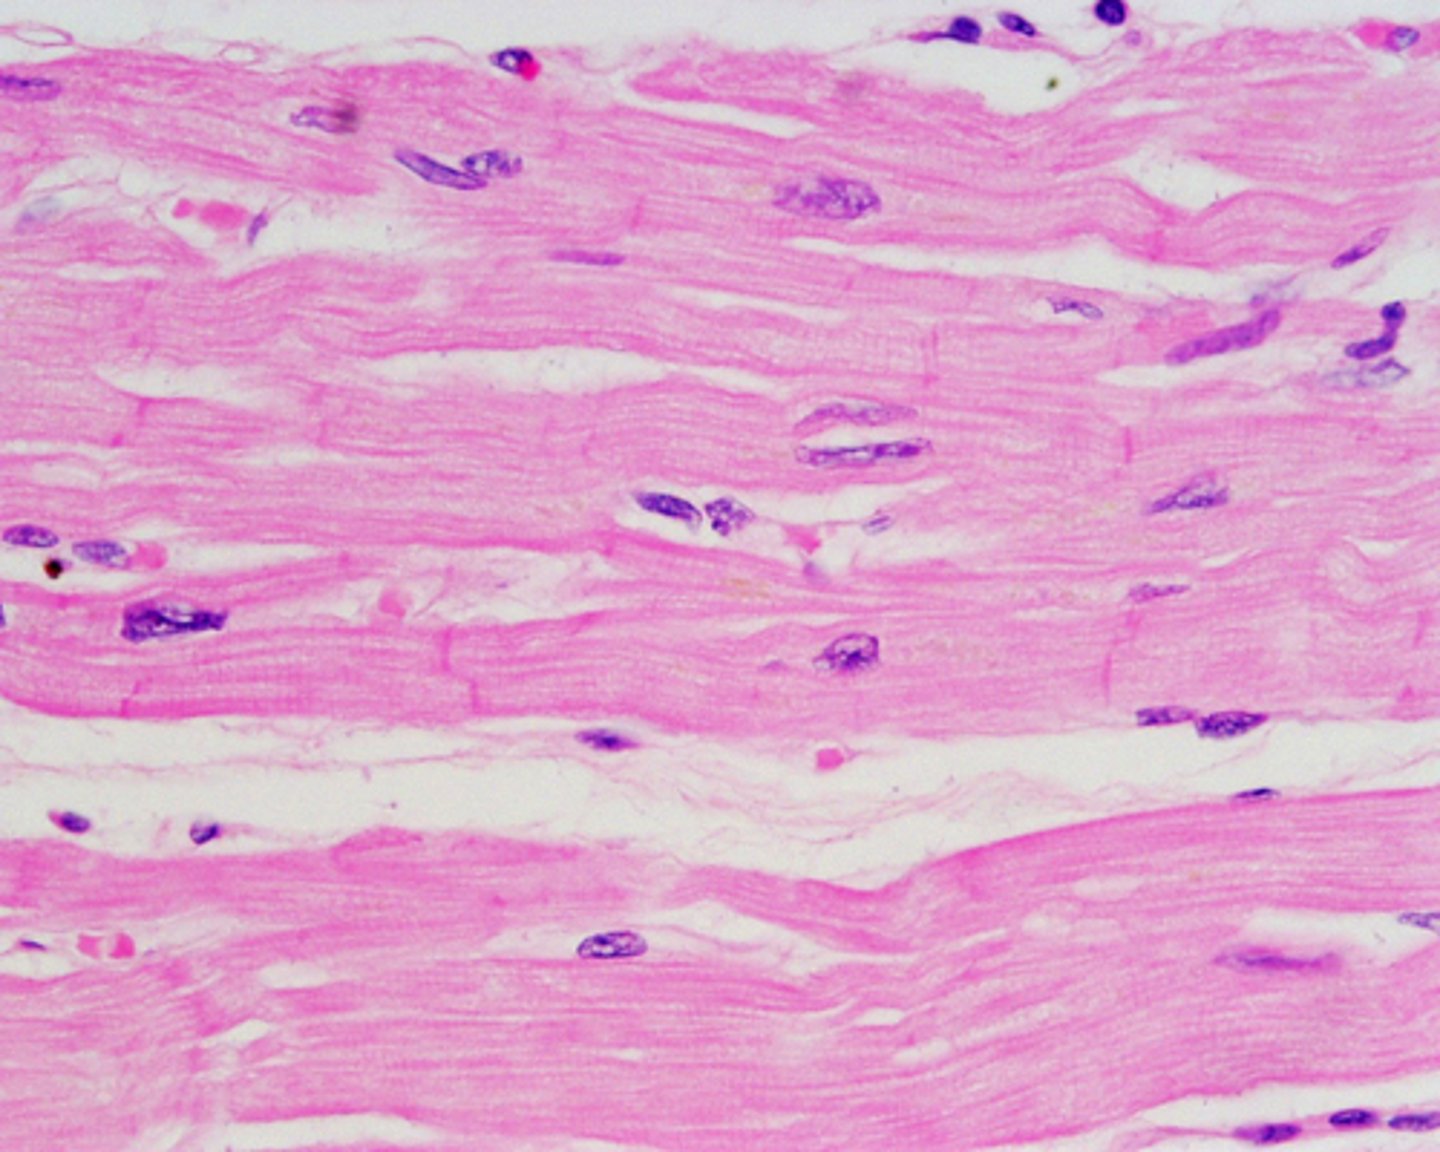

cardiac muscle

location- cardiovascular

function- contracts, propels

Cardiac muscles

in heart

involuntary

propels blood

branched, stripes